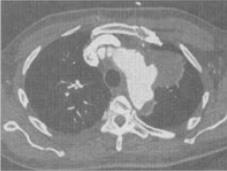

患者男,50岁,胸背剧痛1周余,CT如图,最可能的诊断是()。

A、主动脉弓真性动脉瘤

B、主动脉弓假性动脉瘤

C、主动脉弓夹层动脉瘤

D、左上肺癌并侵犯主动脉弓部

E、纵隔肿瘤

B